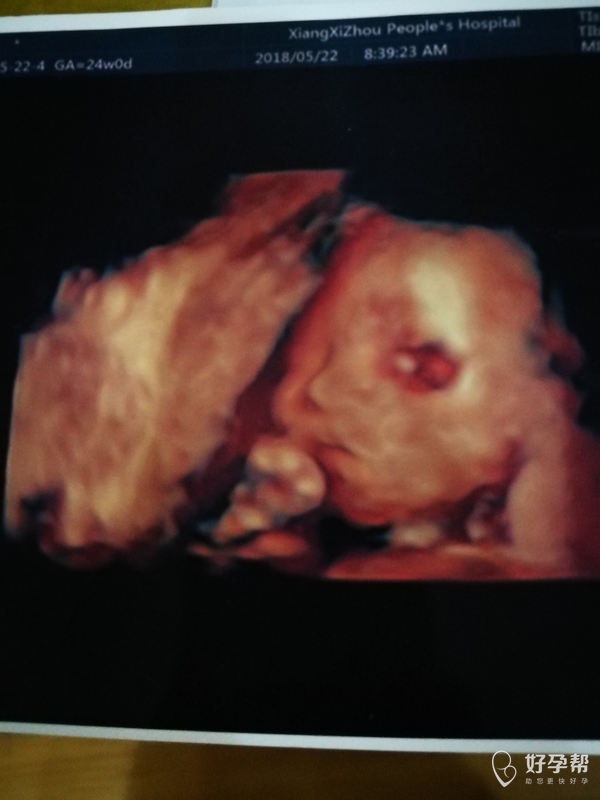

麻烦医生帮忙看看四维结果

请问医生我的宝宝检查结果有什么需要注意的异常吗?还有四维照片眼睛部位为什么这么红像这个样子,希望没什么问题。谢谢了!

你好。脐带绕颈一周。注意胎动情况。一般没事。肾轻度分离小于1观察就行。一般没事。眼睛没事。